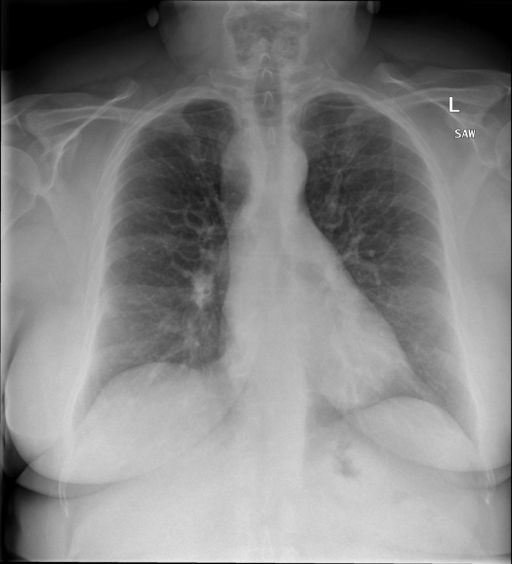

|X光影像|诊疗报告(医生)|XrayGLM|

|:-|:-|:-|

||心影形态在正常范围内。没有急性骨质异常。有可能出现没有明显的吸水或肺实质状况的线索。没有大面积积液或气胸。有可能怀疑其有误吸或肺实质问题。为了确诊和治疗,可能需要进行适当的影像学随访。|心脏大小正常,肺部和纵隔轮廓清晰。没有急性异常或活动受限的证据。没有任何明显的气胸、胸腔积液或肺不张的迹象。此外,也没有发现任何局灶性骨质异常或其他急性疾病。|